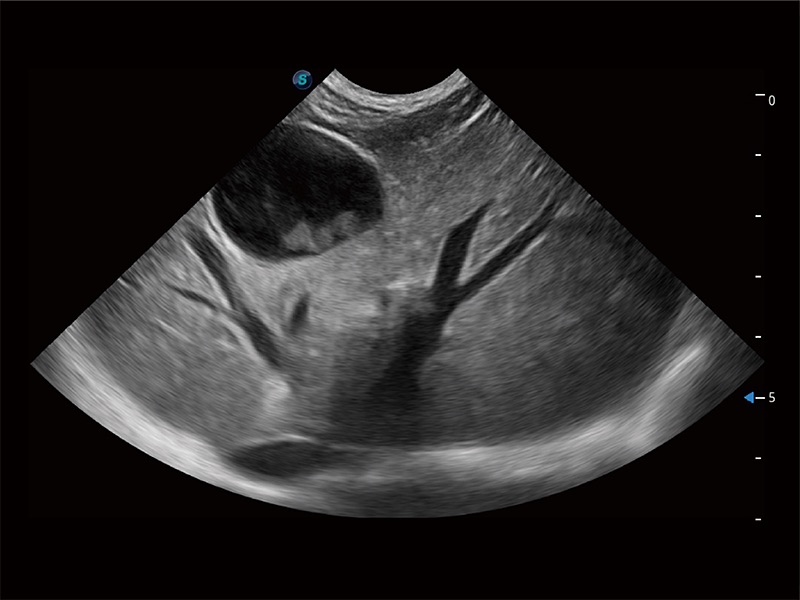

(犬)肝臟

(貓)膽囊

(犬)腸道

(犬)胎兒四腔心